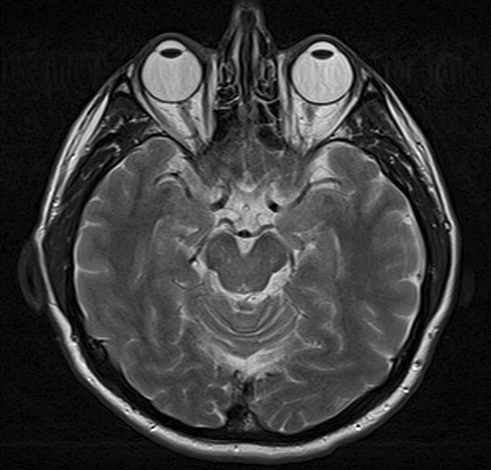

Cette image est une IRM du cerveau. Les globes oculaires de la personne sont visibles en haut de l'image.

IRM

By Ptrump (Own work) via Wikimedia Commons